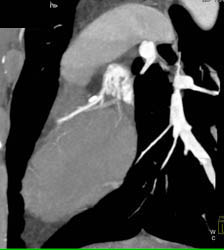

Diseased LAD